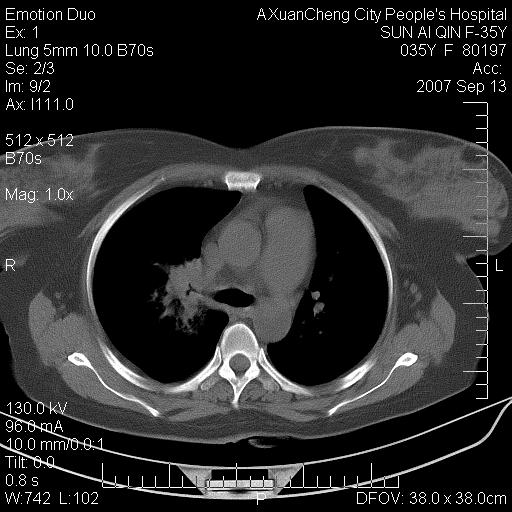

以下是引用天南地北在2007-9-13 13:43:00的发言:[br]考虑双肺、肺门侵润

以下是引用ydx_74在2007-9-13 15:42:00的发言:[br]仅看片,考虑右上肺癌并双肺转移,结合病史,考虑肺门、肺内淋巴侵润

以下是引用同在2007-9-13 15:08:00的发言:[br]支持肺门及双肺侵润.